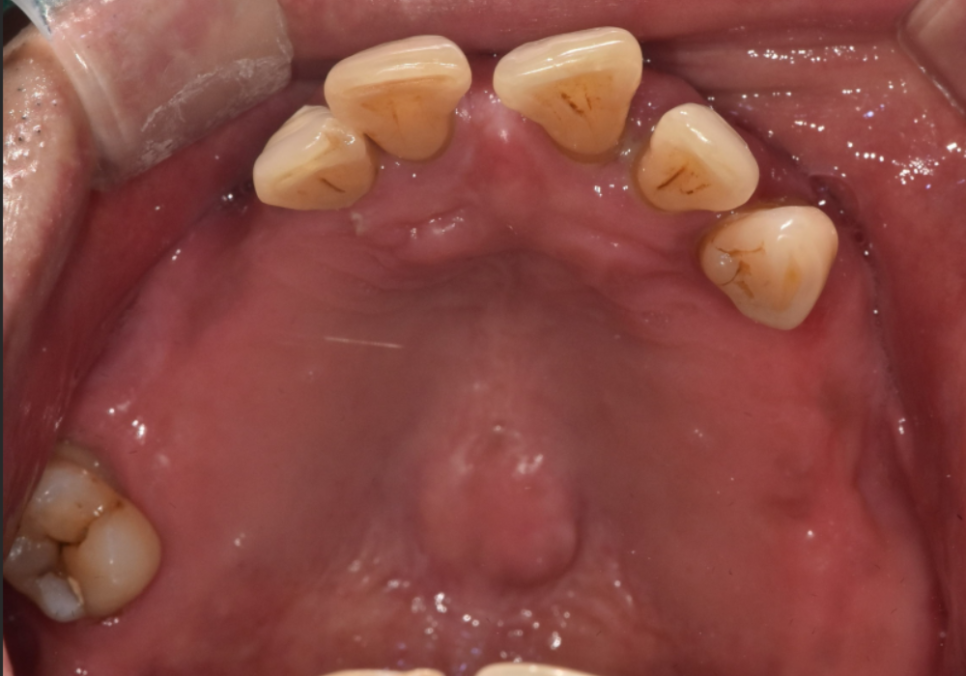

얼마 전 저희 치과를 방문하신 환자분은

앞니 6개(#13~23)가 씹는 힘을

견디지 못해 가운데에

금이 가 있는 상태였습니다.

치아는 마모되어 짧아져 있었고,

씹는 면 쪽은 상아질이 드러나 보일 정도로

마모가 진행되어 있었죠.

240221